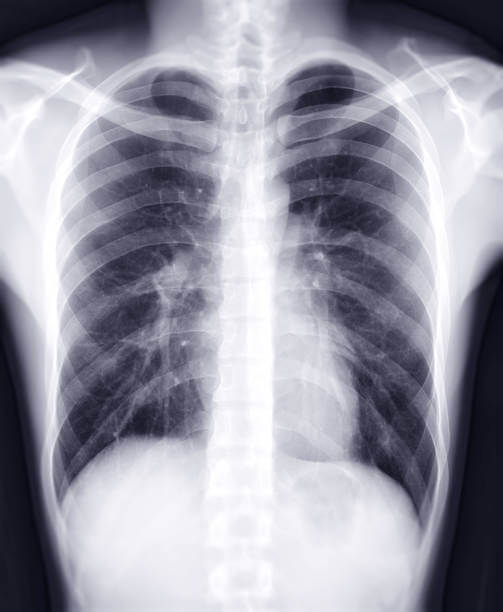

합병증 확인: 폐부종과 관련된 합병증 여부를 확인하기 위해 흉부 X-선, CT 스캔, 혈액검사 등이 수행될 수 있습니다. 이는 폐 이외의 다른 기관과 조직의 상태를 확인하는데 도움을 줍니다.